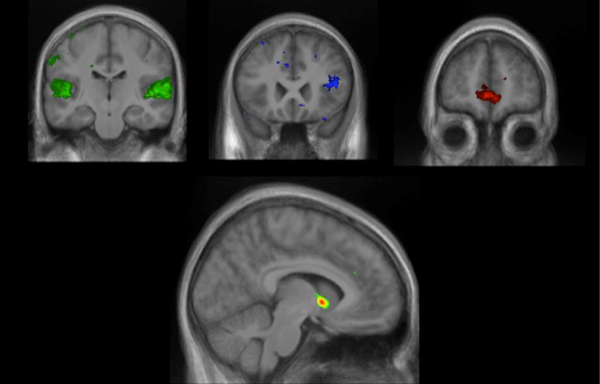

When people hear a new tune they like, a clump of neurons deep within their brains bursts into excited activity, researchers report April 12 in Science. The blueberry-sized cluster of cells, called the nucleus accumbens, helps make predictions and sits smack-dab in the “reward center” of the brain — the part that floods with feel-good chemicals when people eat chocolate or have sex.

The berry-sized bit acts with three other regions in the brain to judge new jams, MRI scans showed. One region looks for patterns, another compares new songs to sounds heard before, and the third checks for emotional ties.

All four brain regions work overtime when people listen to new songs they like, report the researchers, including Robert Zatorre of the Montreal Neurological Institute at McGill University